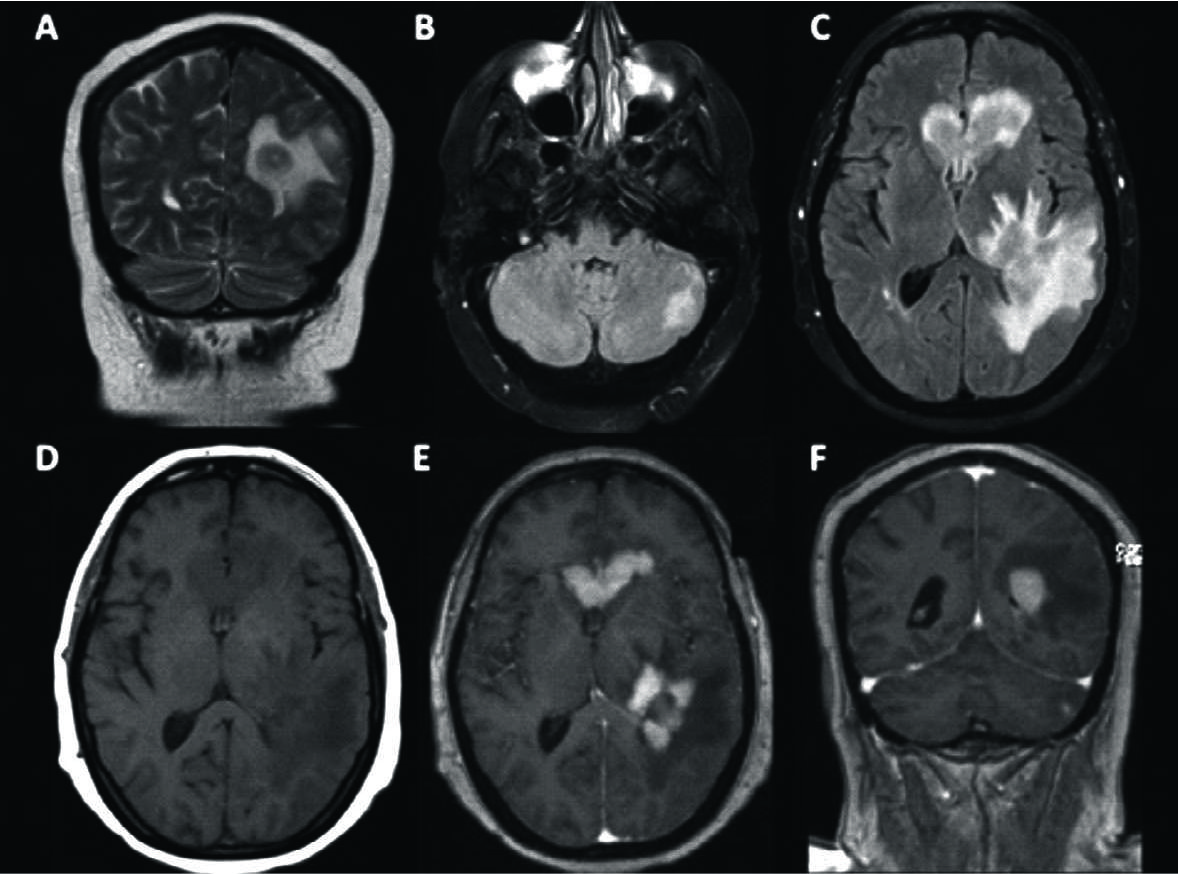

Figura 1

LPSN multifocal con compromiso del cuerpo calloso.

Paciente con diagnóstico de LPSN con múltiples focos de realce, el principal en el CC, sector posterior. Se observa el comportamiento más frecuente: hipointensidad en T1 (A), hipointensa en T2 con respecto a la SG cerebral (B), con edema asociado en FLAIR (C) y restricción en difusión (D). Con el medio de contraste se observa el intenso y homogéneo realce con bordes irregulares (E) y al menos 2 focos adicionales en la sustancia blanca subcortical del lado izquierdo (F).

El cuerpo calloso fue el sector más frecuentemente comprometido. Figura 1 a 3